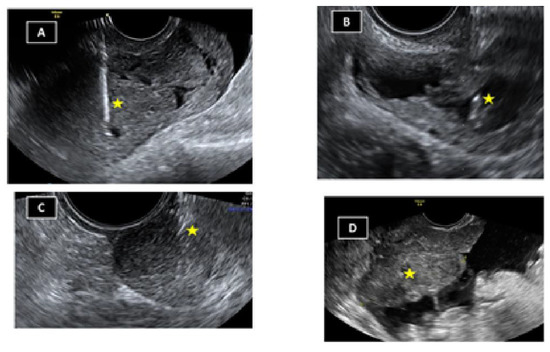

The technique was performed on an outpatient basis in all cases. Before the procedure, 2 g oral azithromycin was administered. The patient is placed in lithotomy position and with the help of a speculum the vagina is aseptized with aqueous chlorhexidine or povidone iodine. The area is then sprayed with lydocaine spray (10 mg/pulsation). Additionally, in some cases, 10 mL of local anaesthesia (mepivacaine 2%) is instilled into the four quadrants of vaginal sac bottom with a spinal needle 22G 90 mm long. The optimal site for puncture/drainage is located by direct visualization of the lesions and with the help of the Doppler those areas with increased vascularization should be avoided. Using the reference guide attached to the transvaginal probe, the procedure is performed (drainage/puncture/biopsy) (Figure 3). The material obtained is sent for pathological, cytological and/or microbiological study if necessary.

Figure 3. Examples of transvaginal ultrasound punctures/drainages/biopsies: (A) Myometrium; (B) tubal abscess; (C) vaginal nodule; (D) ovarian tumor with peritoneal carcinomatosis. Yellow asterisk: Needle.